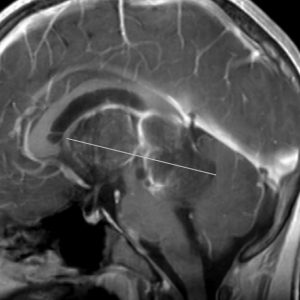

9歳男児の松果体奇形腫です。生検術と第3脳室開窓術を受けましたが,摘出術のリスクが高すぎるということで化学療法を6コース。2年間経過観察されましたが,腫瘍が増大しました。私のところへ来た時には,前後径73mmありました。

左からT2, swan, T1です。これが 類皮のう胞 dermoid cyst ということがわかります。類皮のう胞単独,あるいは成熟奇形腫の大部分としての類表皮のう胞は,かなり頻度の高いものです。松果体腫瘍で奇形腫を疑ったらまず,類皮のう胞の混在を疑います。それがあれば,かなりの確率で成熟奇形腫 mature teratomaです。

類皮のう胞は内部がほとんど皮脂,ケラチン,汗,毛髪なので,簡単に砕けるし,掻き出し吸い取ることができます。松果体成熟奇形腫の中では最も戦いやすい相手と言えるでしょう。再発しないようにするには,周囲ののう胞壁(真の腫瘍細胞)を完全摘出するしかありません。放射線も化学療法も何も効かないし,のこせば必ず再発します。

右迂回槽にちょっとdebrisは残っていますが完全摘出できました。病理は他の成分を少し混じる成熟奇形腫です。術後3年間再発はありませんし,学校へ通って体育もできています。

この手術はもちろん簡単ではありません,でもほとんどが類皮のう胞であるということがわかったので踏み込めたのです。